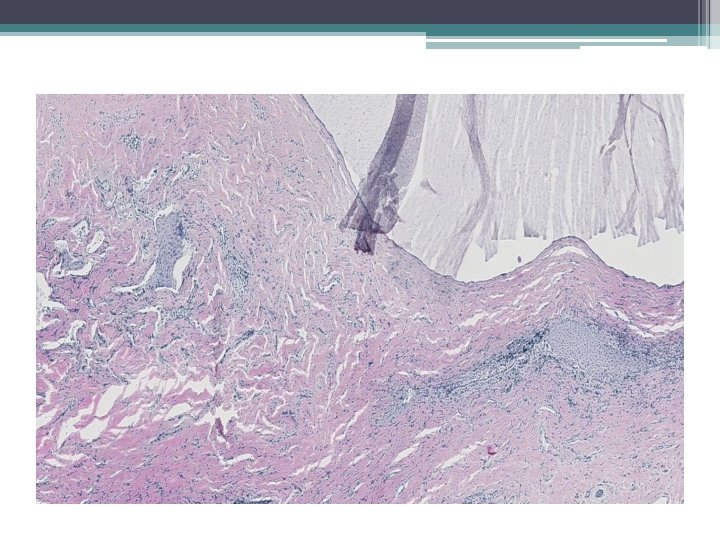

Mikro:

Ektopická prostatická tkáň • • vzácně lokalizace: cervix, vagína věk 21 -65 let mikroskopicky : tubuly a aciny některé papilární, některé kribriformní, s dlaždicovou metaplázií

• Mikroskopicky: • dobře ohraničená hnízda s vrstevnatým dlaždicovým epitelem a tubuly vystlané jednou až dvěma řady kubických buněk, nebo dlaždicovými buňkami. V centru hnízd může byť přítomná nekróza s kalcifikací, nebo keratinové perly.